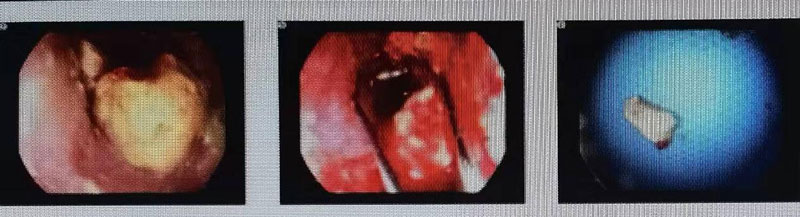

本例患者為80歲女性,確診食管鱗癌,因進(jìn)食困難在當(dāng)?shù)蒯t(yī)院給予營(yíng)養(yǎng)、補(bǔ)液等對(duì)癥治療,后進(jìn)食困難進(jìn)一步加重,面湯及水均不能通過(guò),遂就診我院腫瘤科。請(qǐng)消化內(nèi)科劉慶民主任行“電子胃十二指腸鏡檢查”,鏡下見(jiàn):食道中段見(jiàn)隆起性病灶,大量食物殘?jiān)媪?,用異物網(wǎng)籃取出,內(nèi)鏡不能繼續(xù)通過(guò)。